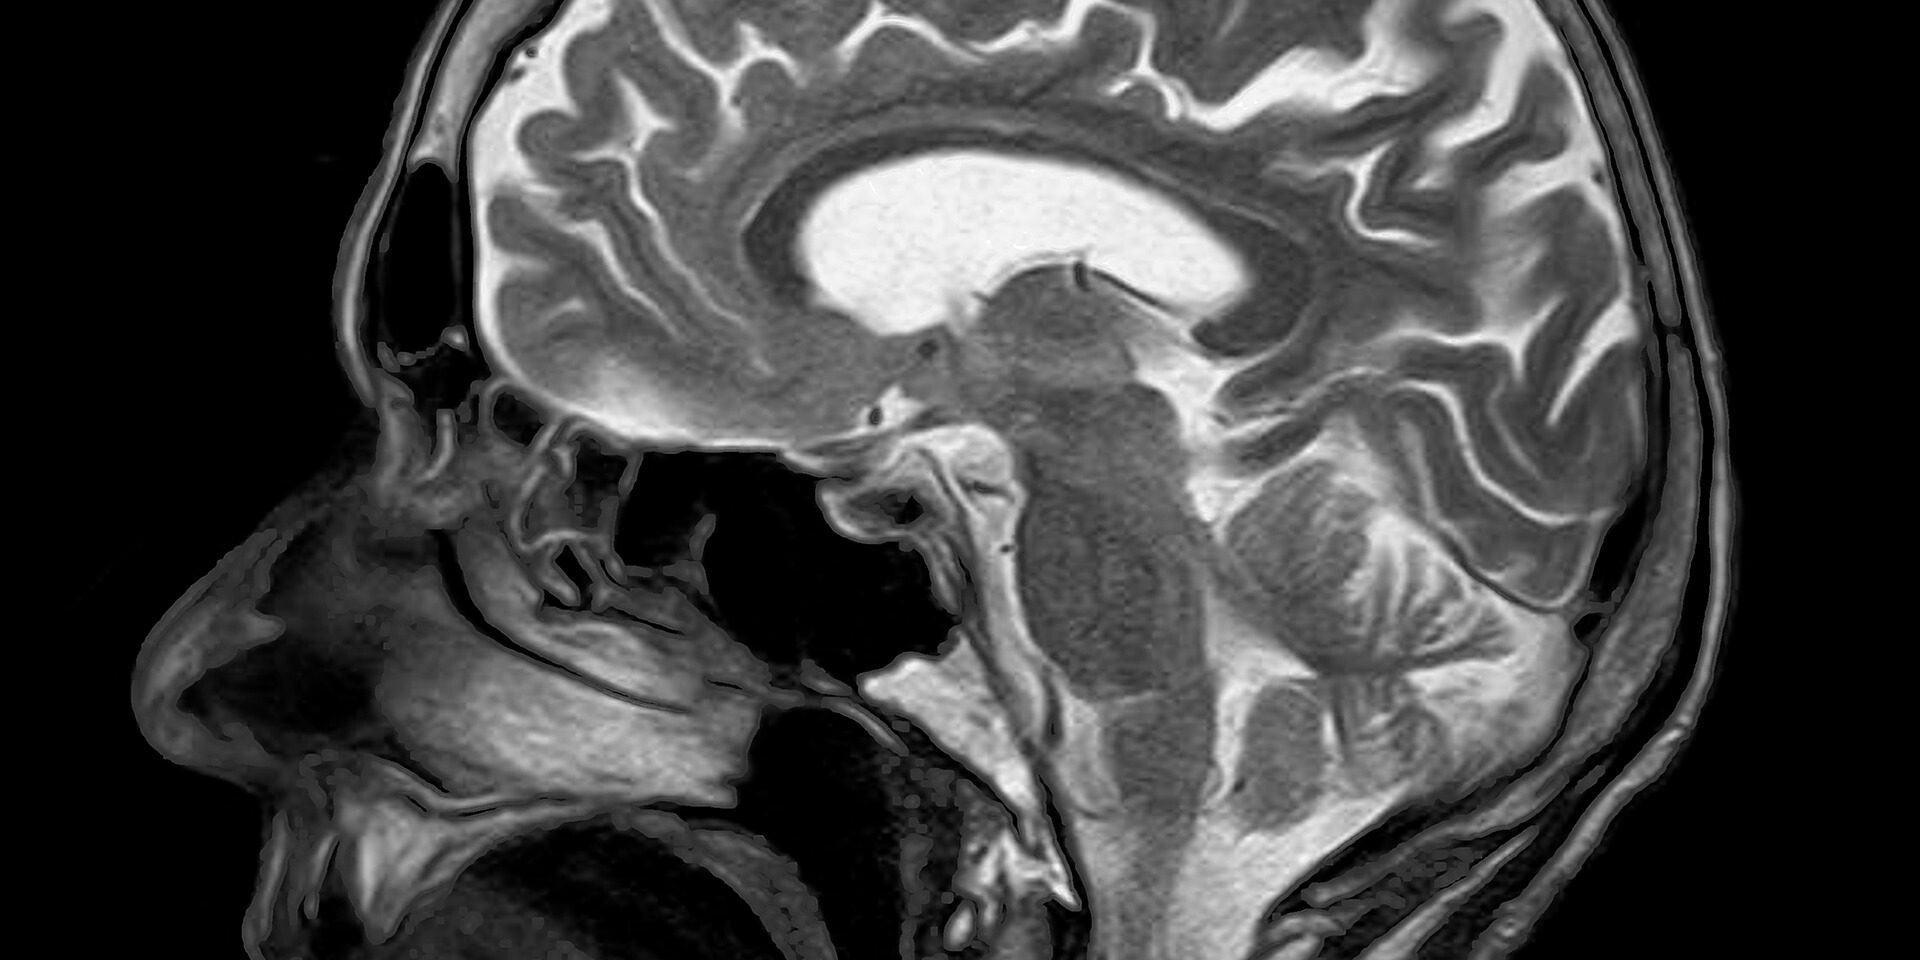

A brain concussion is a sudden and quickly resolving trauma of the brain’s function, secondary to a traumatic brain injury or all impact on the body, transmitting significantly slowed response to the brain. A concussion is a serious event, but you can recover fully from such an injury if the brain is given enough time to rest and recuperate.

Each case of brain concussion is unique. With a direct impact, we must examine the surface of contact and the long-distance repercussions throughout the whole body. Progress will be seen when a certain number of mechanisms are returned to normal function and they begin to interact together once more.